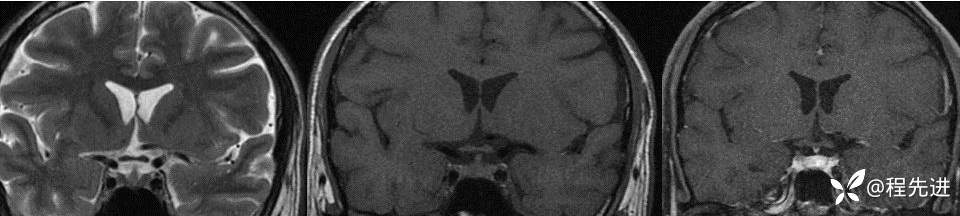

【患者信息】:男,49岁

多尿、烦渴、多饮3月,恶心2月余

辅助检查:血渗透压:Sosm314mOsm/kgHO,尿渗透压:435mOsm/kgH0,尿比重1.011,Na149mmol/L